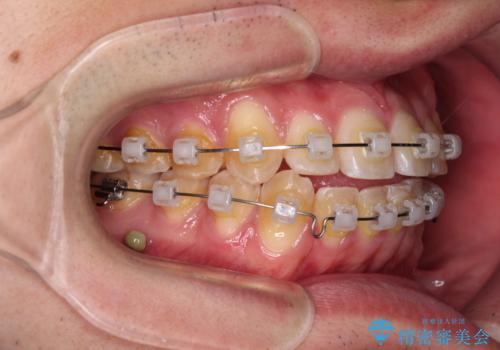

八重歯と前歯のクロスバイト ワイヤー装置で短期間矯正

- クリアブラケット

上顎側切歯(前から2番目の歯)が内側に転位している歯列は、インビザラインでは排列が困難であることが多いため、期間を短く、より良い仕上がりとするため、ワイヤー装置にて矯正治療を行うこととしました。

治療開始の頃は、食事や歯磨きが慣れず、装置が頻繁に脱落しましたが、2,3ヶ月ほどで慣れ、その後は1年ほどで治療を終えることができました。